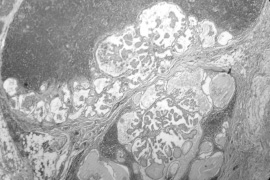

Рис. 1,2. Нативные препараты.

Разные размеры папиллярного рака щитовидной железы